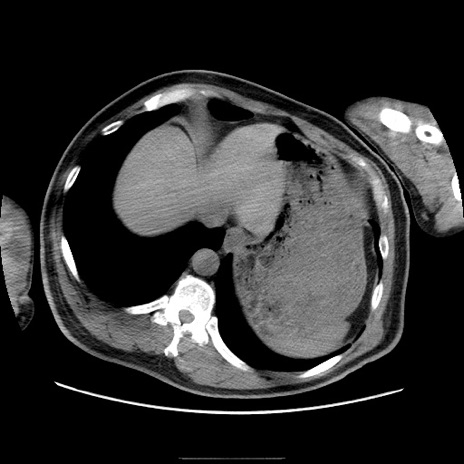

症例

冠状断像